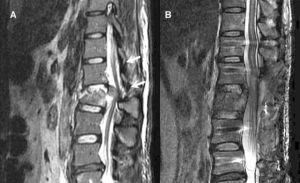

馬尾神經損傷馬尾神經受損,肛門會陰部及下肢出現異感、燒灼樣痛,重者可發生大小便障礙,給患者帶來極大的不便。馬尾神經根損害時,可以表現為腰2以下各種神經損害症狀。全馬尾損害時,感覺障礙分界清楚,上界前為腹股溝,後為髂骨上端的水平線,在此以下,臀部、會陰及下肢全部出現感覺障礙,伴有自發痛(電擊痛)、會陰有異常感覺並向下肢放射,常有痛性感覺遲頓。馬尾損害的高度、程度不同,其上、下界可有不同。

多見脊柱暴力骨折、腰椎退行性病變、馬尾部位膽脂瘤、神經鞘瘤、脊髓脊膜瘤、脂肪瘤或轉移瘤刺激損傷馬尾等。目前西醫治療主要以手術切除突出椎管內被壓縮骨折的椎體骨片、脫出的椎間盤以及刺激馬尾神經的腫瘤為主,輔以脫水劑、皮質激素、營養劑或自由基清除劑等,有一定的效果,但有一定局限性。